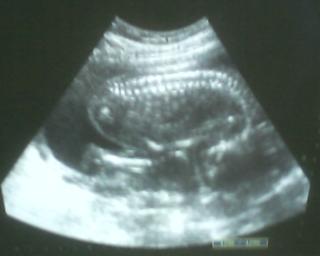

@lusinda1989 tak to máš pravdu.....ale pekne to letí - ved takto o 4 dni, už budem v 6. mesiaci 🙂 dnes sme boli na poradni, tak som vzala aj manžela so sebou, aby videl to malé šidlo v brušku.....doktor mu všetko pekne poukazoval, pozeral aj na pohlavie, ale určitosťou nám ešte nevedel potvrdiť - no ale vyzerá to tak, že to bude chlapčiatko 😀 ach jáááj tie poradne sú super 🙂 😉

Ahojte.Dam update aj tuna : Vcerajsie morfo na vybornu,je to dievcatko,nasa BAMBULKA,ma 362g a okolo 25cm.Manzel bol pri mne,potesil sa.Termin upraveny na 21.9. (+/- 8 dni)

@dadika663 ahoj moja tak mi mame uz sono za sebou.budeme mat chlapceka 😀 😀 vsetko ok.juj tak to bolo krasne vidiet drobca,ze slzy mala na krajicku.

@kucharikova je to krasne vidiet svoje miminko aj ne sa zakazdim tisnu slzy do oci a nas tatinko ma vzdy drzi za ruku ked sme dnu na sone.

@nmonika tvoj pokladik jak si vegeti po styroch.moj maly zas vegetil na chrbatiku a pravu rucinku si drzal hore a pozeral ako si hybe s prstikmi 😀 😀

@kucharikova jee,to muselo byt tiez nadherne.A nemas fotku?

Sestrin chlapcek bol este aj presne ulozeny ako nasa bambulka,takze mame rovnake foto.